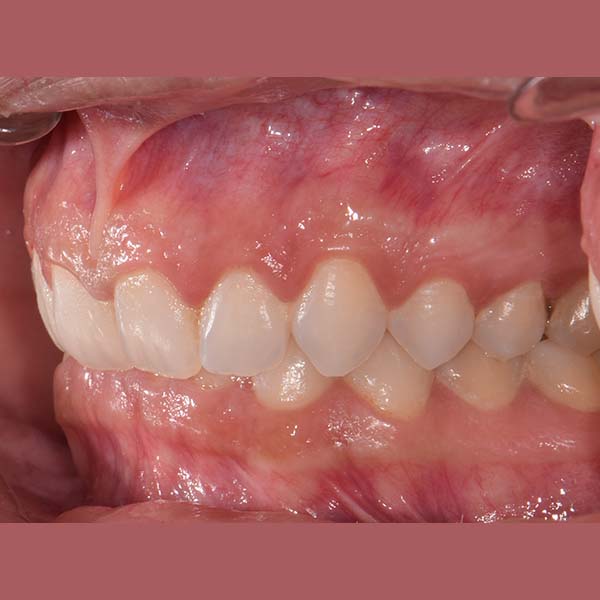

AFTER

Our lady was treated using fixed braces, the tilt in her upper front teeth was adjusted, and the space of their coverage was reduced.

At the end of the treatment, she was able to smile with comfort and confidence again